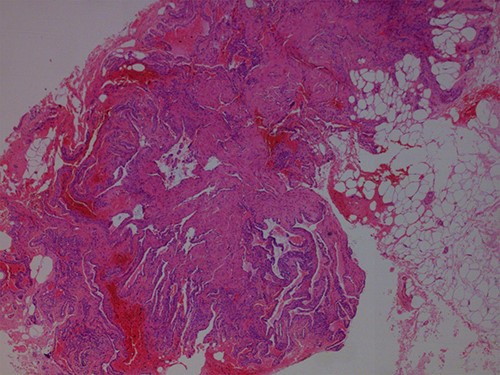

During the procedure tumors were removed completely and subsequently ordered pathological examination confirmed the diagnosis of a GT (Figs 3–5). The report documented the presentation of benign tumors with dilated vessels, surrounded by collars of glomus cells with adjacent hyalinized stroma. The operation was uneventful and on a follow-up visit 6 months later, the patient was completely pain free, with no evidence of local recurrence (Fig. 6). However, a similar lesion was found on the left side of the patient’s lumbar region.

Hematoxylin and Eosin ×40: pieces of neoplasm with adjacent fatty tissue.